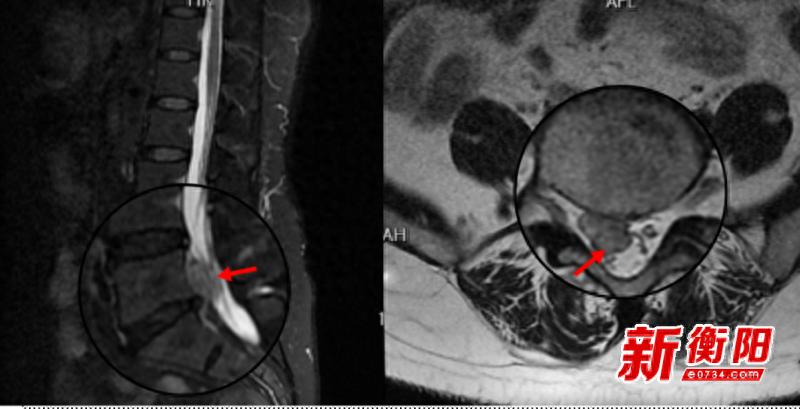

【来源:衡阳新闻网_热点关注】衡阳新闻网讯 通讯员王璐报道近日,衡南县人民医院骨科二区团队在中南大学湘雅三医院苗惊雷教授的指导下...